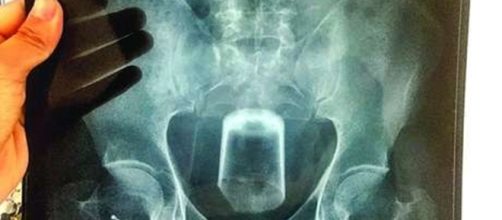

Os médicos confirmaram toda a história do homem através dos exames de raio x realizados. Era possível observar nitidamente a imagem do copo entalado na região do reto.

Os profissionais do BMJ Case Reports afirmaram que o copo estava com a parte inferior para cima, ou seja, de cabeça para baixo. Os exames que foram realizados no italiano mostraram pequenos fragmentos de vidro dentro do organismo.